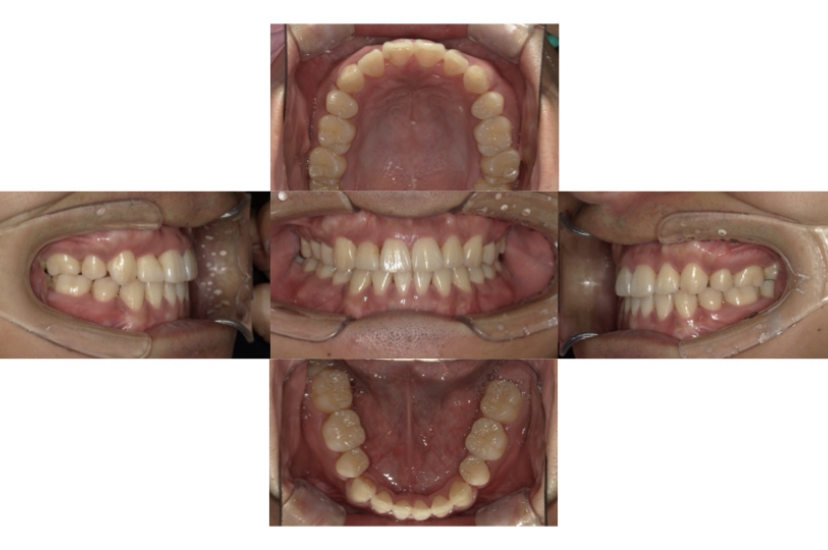

AFTER

上下顎叢生(上下の前歯のガタガタ)のケースです。

装置はラビアル(上下表側)で、上下顎の小臼歯を4本抜歯を行っています。抜歯したスペースを利用し、上下の前歯の後方移動と叢生(ガタガタ)の改善を行っています。歯科用アンカースクリューを使用することで、可能な限り前歯を後方移動させています。

主訴 上下の前歯のガタガタで歯が磨きづらい。

年齢・性別 16歳 男性

お住まいの地域 東京都中央区

治療方針 抜歯スペースを利用して上下前歯の叢生(ガタガタ)の改善

抜歯部位 上下顎左右第一小臼歯

使用装置 ラビアル(上下表側)、顎間ゴム、歯科用アンカースクリュー

治療期間 2年3か月

治療回数 24回

リテーナー クリアリテーナー